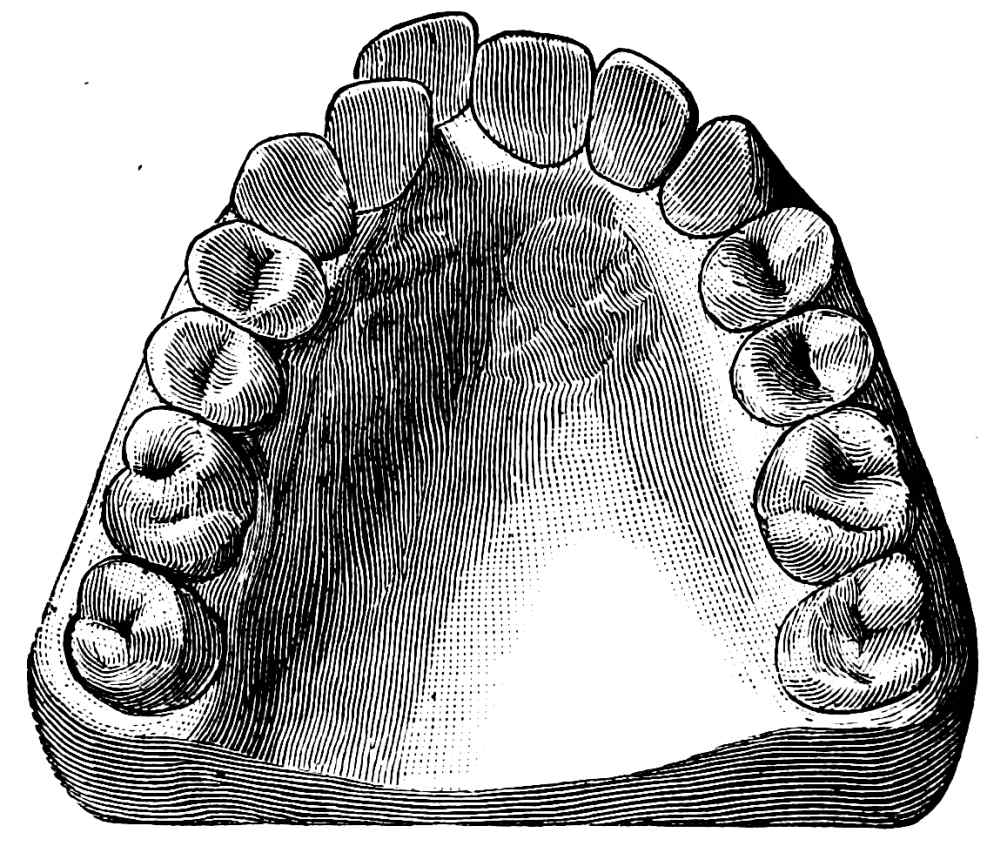

(d) Lower Molars.—Lower molars have two roots, placed anteriorly and posteriorly. The roots are much flattened and have a tendency to curve backwards, this being well marked in the second and especially so in the third molar; a fusion of the two roots is at times met with in the second and frequently in the third molar. A section of a lower molar at the neck shows both the buccal and lingual aspects to be composed of two segments of a circle touching each other at one extremity; the anterior segment being slightly the larger (fig. 28). Each blade of the forceps used for these teeth should possess two grooves,{36}

separated by a projection which fits into the division between the anterior and posterior roots; for all practical purposes the blades may be made of the same size, so that one instrument will suffice for both sides of the jaw. The instrument best adapted for the removal of these teeth is shown in fig. 29, though some operators prefer the shape illustrated in fig. 30. The advantages of the{37} former over the latter may be briefly summed up as follows:

(1) A clear view of the tooth and its surroundings can be obtained during the whole period of removal.

(2) Force can be applied with greater advantage.

(3) The alveolus can be easily embraced by the fingers, or by the finger and thumb of the left hand.

(4) In removing the tooth from the socket a slight backward movement can be employed.

One disadvantage of shape fig. 29 is that it is difficult to employ much inward movement, and therefore, for teeth lying inwards, namely, with the crown directed towards the tongue, hawk’s-bill-shaped forceps cannot easily be used.

Another disadvantage is that the extent of inward movement is limited by the proximity of the upper teeth, and in case of trismus it is often better to use straight forceps (fig. 30). In cases where there are also much swelling and rigidity of the cheek the straight forceps cause less inconvenience to the patient.

In removing lower molars with forceps, the inner blade should be first applied and then the outer, care being taken to get the points of the blades between the interspace of the roots. For severing these teeth from their attachments, a slight inward movement should be first made, followed by one well outwards, this inward and{38} outward movement being repeated if necessary. The removal of the tooth from its socket is carried out by force used in an upward and outward direction. The upward force exerted upon lower teeth should always be well under control, as not infrequently the resistance is very suddenly overcome, and, if such precaution is not taken, there is danger of striking the upper teeth with considerable force.

As previously pointed out, the roots of these teeth are at times curved a little backwards so that it is often needful in removing the teeth from their sockets to twist the forceps in a curved direction backwards.

In the removal of the second molar too much outward movement is not permissible, as the outer alveolus is often very dense.

The third molar is best removed with a straight elevator. A glance at the illustration of this tooth (fig. 31) will show that the roots have a well-marked curve backwards, in addition to which the bone forming the socket of this tooth is stronger than is the case with the anterior molars. The removal of the third molar has therefore to be accomplished by using force in a direction upwards and backwards, in other words, in a curve similar to the arc of the circle formed by the roots. This movement cannot well be carried out with forceps, but is easily accomplished with the elevator as follows (it being assumed that the second molar is in place):—Hold the elevator as shown in fig. 13, and insert the blade between the anterior surface of the root and the alveolus, keeping the flattened side of the instrument as far as possible parallel with the root surface. Then force the blade downwards in a direction towards the apex of the root; following this, rotate the handle away from the direction in which the tooth is to{40} be moved. This has the effect of both raising the tooth in its socket and displacing it backward. The edge of the elevator which is to be brought into contact with the surface of the root should be sharp so as to cut somewhat into the cementum. Should this prove insufficient the handle should again be raised and the flattened surface of the instrument brought parallel with the anterior surface of the root and the extractive movement repeated until the tooth is completely raised from its socket.